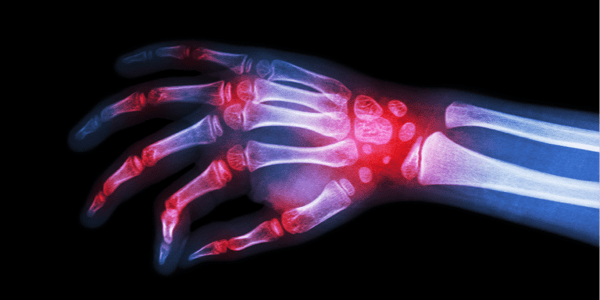

사실 위와 같은 A씨의 사례는 주변에 중년 연령대의 가족이나 지인이 있다면 어렵지 않게 접할 수 있는 내용이기도 합니다. 보통 관절염이라고 하면 무릎에 생기는 것으로 알고 있지만, 관절염은 모든 관절 부위에 발생할 수 있는 질환이며, 그 부위가 손가락이라면 손가락 관절염이 발생 할 수 있습니다.

손가락 관절염은 오랜 시간 동안 손가락을 많이 사용하여 손가락 부위의 연골이 닳거나 관절낭의 퇴화로 생기는 퇴행성 변화가 가장 큰 원인으로 알려져 있습니다. 손가락 관절이 붓거나 염증에 의해서 주로 손가락 끝 마디 부분에 통증이 나타나는데 진행이 될수록 손마디가 굵어지는 것을 확인 할 수 있습니다. 보통 손가락 관절염은 천천히 진행되므로 주로 중년 이후에 잘 나타나지만, 손가락을 지나치게 사용할 경우 나이와 관계없이 손가락 관절염이 발생할 수 있습니다. 따라서, 대부분 손을 이용하여 작업하는 스마트폰이나 컴퓨터를 자주 사용하는 젊은 층에서도 발병할 수 있으니 주의가 필요합니다.